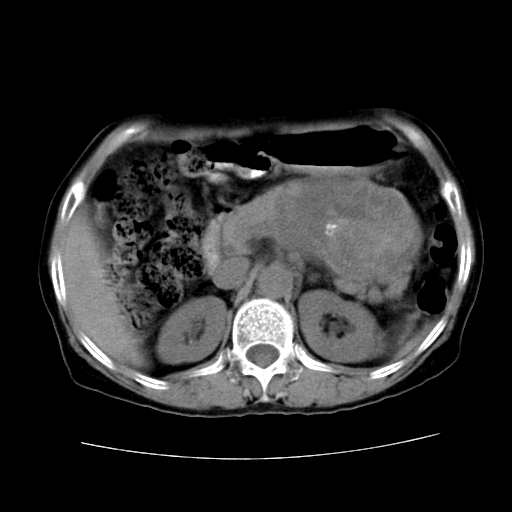

女性,72岁。

主诉中上腹部疼痛不适1年余。

胰腺尾部不规则巨大略低密度肿块,界限清楚,内密度不均,增强动脉期不均匀强化,门脉期明显退减并低于胰腺密度,肿瘤包埋于脾血管。多考虑;来源于胰腺尾部的“胰腺癌”。

胰腺尾部不规则巨大略低密度肿块,界限清楚,内密度不均,增强动脉期不均匀强化,门脉期明显退减并低于胰腺密度,肿瘤包埋于脾血管。多考虑;来源于胰腺尾部的“胰腺囊腺癌。

该例有几个特点需注意:

1.肿瘤大而边界清

2.内部有钙化

3.强化时间较长

4.这么大的肿瘤对周围的血管无侵犯

以上几条均与胰腺癌不符

故考虑:胰岛细胞癌

1、这个病例确实有点难。影像主要显示胰腺体尾部占位,我们当初也是诊断胰体尾部囊腺癌可能性大,而且读片会上也很多人这么诊断的。

2、手术所见:打开腹腔发现胃与胰腺体尾部可见肿块,大小约10×8×11cm,质硬,不可推动,周围血供丰富。术中诊断:胃肿瘤侵及胰腺体尾部。

1)、胃小弯侧胃肠间质瘤(考虑恶性),瘤体大小13.5×7×6.5cm,上下切缘阴性。

2)、胃小弯1只、幽门下2只淋巴结慢性炎。免疫组化:cd117(+)、cd34(+)、sma(+)、desmin(-)、s-100(-)、ki-67<10%(+).

4、这个肿瘤太大了,而且密度不均性强化,从这点我们应该不能单纯诊断胰腺癌,而应想到目前流行的胃肠道间质瘤。这个肿瘤主要发生于胃壁浆膜层,所以显示与胃壁关系不是很紧密,故而大多认为是胰腺癌。